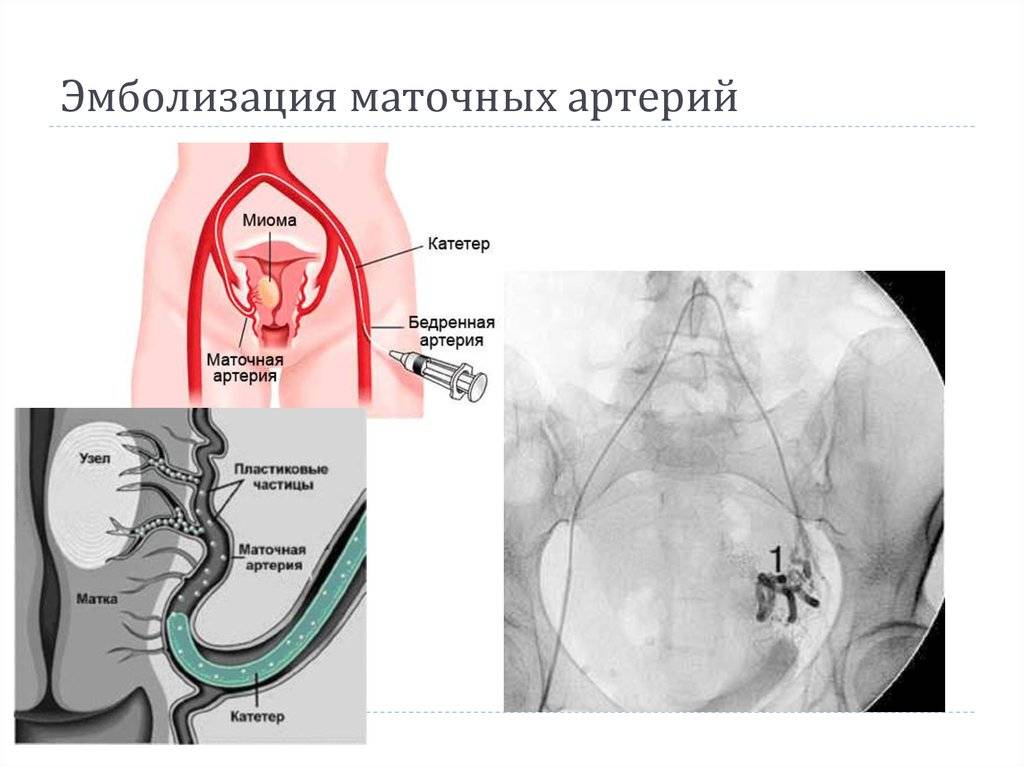

Хирургические процессы при эмболизации гемангиомы на фото